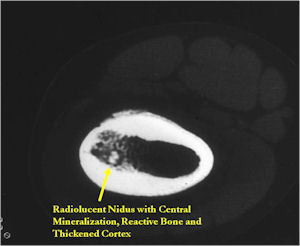

CT Scan:

- Well defined nidus with a smooth peripheral margin; +/- mineralization (CT more sensitive than XR and MRI for detecting mineralization); CT is better for detecting nidus in presence of exuberant sclerosis

- Lucent nidus surrounded by a zone of marked sclerosis

- The nidus may demonstrate mineralization/ossification usually from the center outward that appears as a central zone of density within the nidus